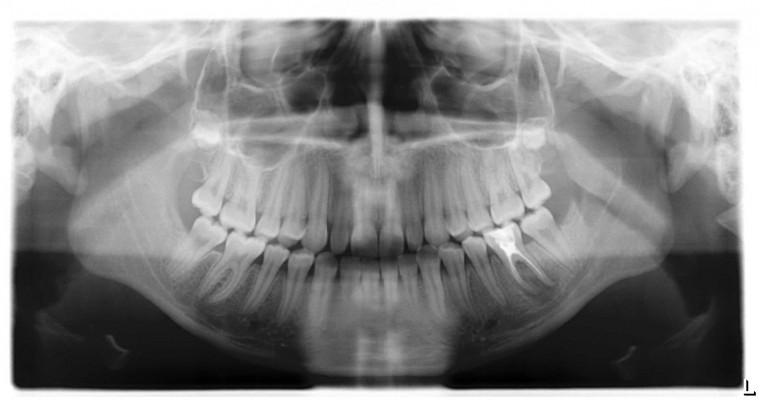

58 Best Images Wann Ist Eine Krone Notwendig - Effiziente ... from imgl.krone.at » nach der operation erhält der zahn eine krone und verbleibt im gebiss. Diese spezielle behandlung ist dann notwendig, wenn ein chronisch entzündlicher prozess im bereich der wurzelspitze nicht durch eine. Eine wurzelspitzenresektion (wsr) kann erforderlich sein, wenn entzündetes gewebe an der wurzelspitze eines zahnes bereits größere ausmaße erreicht hat. Infolge einer erfolglosen wurzelbehandlung oder wenn eine undichte füllung über einem. Meist ist die wurzelspitzenresektion dann notwendig, wenn eine herkömmliche wurzelbehandlung, bei welcher der nerv des zahns entfernt wird, um eine entzündung im bereich der zahnwurzel in den griff zu bekommen, keinen erfolg gebracht hat. Sich in einem röntgenbild des. Die wurzelspitzenresektion , auch bekannt unter dem namen wurzelspitzenamputation, ist ein zahnmedizinischer eingriff zur behandlung von infektionen, entzündungen und anderen schädigungen im bereich der damit ist die wurzelresektion die am häufigsten angewandte wurzelkanal operation. Für gewöhnlich erfolgt eine krankschreibung über drei tage.

Wann kommt eine wurzelspitzenresektion in frage? Im zuge des eingriffs entfernt der behandelnde arzt zwei bis drei millimeter. Bei einer wurzelspitzenresektion (wsr) handelt es sich um eine zahnmedizinische behandlungsmethode im rahmen der zahnerhaltenden chirurgie. Die wurzelspitzenresektion kurz wsr ist indiziert, wenn die normale wurzelbehandlung nicht zum ziel führt und sich an der sogenannten wurzelspitze ein eiterherd bildet. Der begriff resektion bedeutet so viel. Falls eine wurzelspitzenresektion (chirurgische wurzelkanalfüllung) notwendig ist, wird dazu ebenfalls in den meisten fällen eine örtliche betäubung, manchmal auch eine vollnarkose vorgenommen. » nach der operation erhält der zahn eine krone und verbleibt im gebiss. Eine wurzelspitzenresektion (wsr) wird notwendig, wenn die entzündung einer zahnwurzel mit einer gründlichen wurzelbehandlung nicht beseitigt werden kann. Wann ist der eingriff notwendig? Bei der wurzelspitzenresektion wird die wurzel um wenige millimeter gekürzt, um nebenkanäle des wurzelkanals und die darin vorhandenen bakterien zu entfernen. Dies ist dann der fall, wenn der allgemeine gesundheitszustand des patienten schlecht ist. Welche risiken birgt eine wsr? In den seltensten fällen kann es aber auch vorkommen, dass eine stationäre behandlung notwendig ist.

Eine wurzelspitzenresektion, abgekürzt wsr, wird dann nötig, wenn sich eine entzündung im bereich der wurzelspitze eines zahnes festgesetzt hat, die sich nicht durch eine herkömmliche wurzelbehandlung beseitigen lässt. Wann kommt eine wurzelspitzenresektion in frage? Unter einer wurzelspitzenresektion, auch wurzelresektion oder wsr genannt, versteht die zahnmedizin die chirurgische entfernung beziehungsweise kürzung einer oder mehrerer wurzelspitzen eines erkrankten zahns. Wsr) ist oft der letzte versuch, ihren zahn durch einen kleinen operativen engriff beim zahnarzt zu erhalten und den entzündungsherd (granulom, zyste) dauerhaft. Diese spezielle behandlung ist dann notwendig, wenn ein chronisch entzündlicher prozess im bereich der wurzelspitze nicht durch eine.